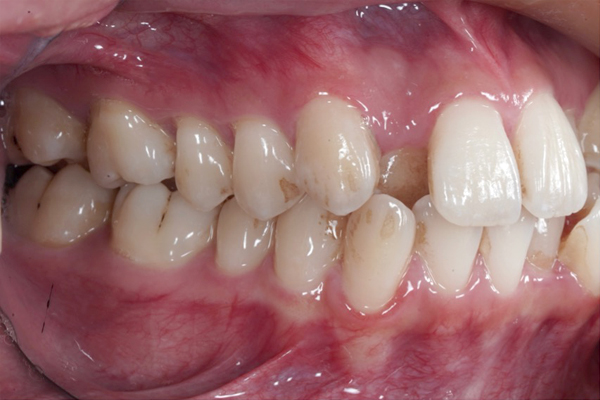

BEFORE

AFTER

• ずっと叢生(ガタガタ)が気になっていた。

• ワイヤー矯正でスペースを作り、非抜歯(抜歯をしないで)並べていく治療方針を計画しました。

• 前歯の重なりが減り、アーチが広がってきました。